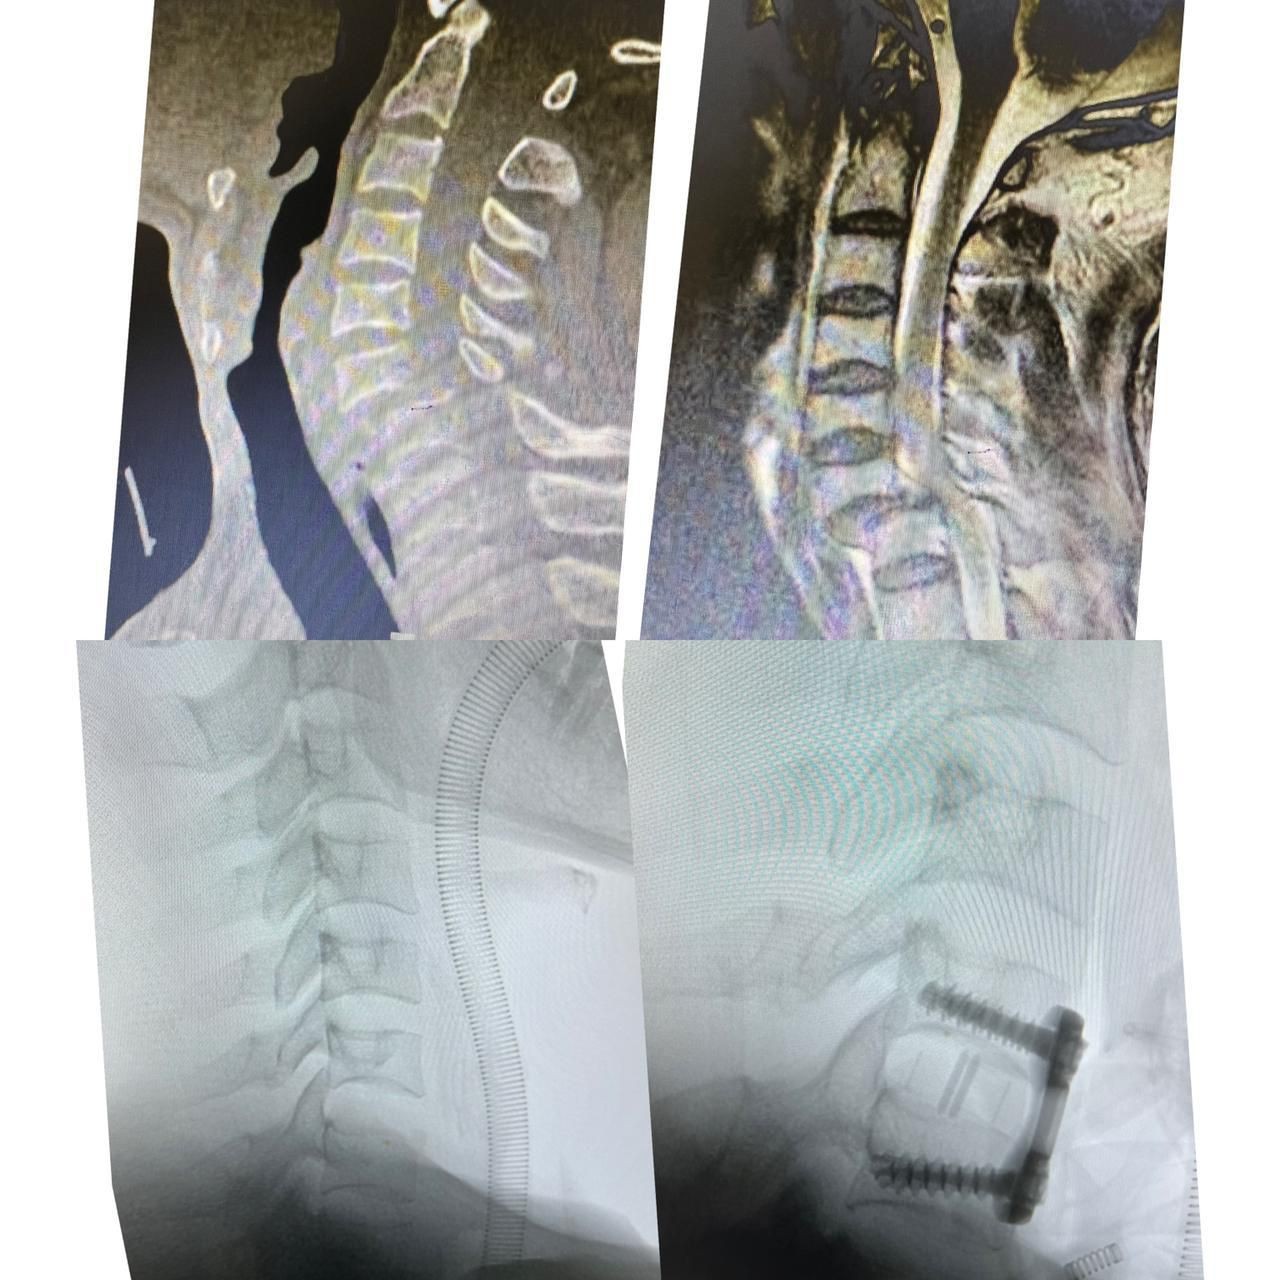

وأوضح الفريق الطبي المعالج ان المريض كان قد وصل لطواريء المستشفى بعد اصابته في حادث مروري أدى الى اصابته لخلع كامل للفقرة العنقية السادسة والسابعة مع ضغط كامل للحبل الشوكي مما سبب شلل رباعي كامل للاطراف.

هذا وقد قام اطباء العظام المختصين بمستشفى الملك فهد وعلى الفور وفي وقت وجيز من تجهيز المريض لغرفة العمليات بعد ان عمل له اشعة الرنين المغناطيسي والفحوص اللازمة حيث اجريت له عملية جراحية عاجلة لمنع حصول شلل دائم للمريض.

وقد تم ارجاع خلع الفقرات العنقية وتحرير الحبل الشوكي وتثبيت الفقرات والمتابعة للمريض بعد نقله للعناية المركزة.

ومن جهة ثانية وذات السياق ابدى المريض تحسنا كبيرا في حركة الاطراف العلوية والسفلية اضافة الى التاهيل الطبي له حتى رجوعه الى حالته الطبيعية باذن الله تعالى.